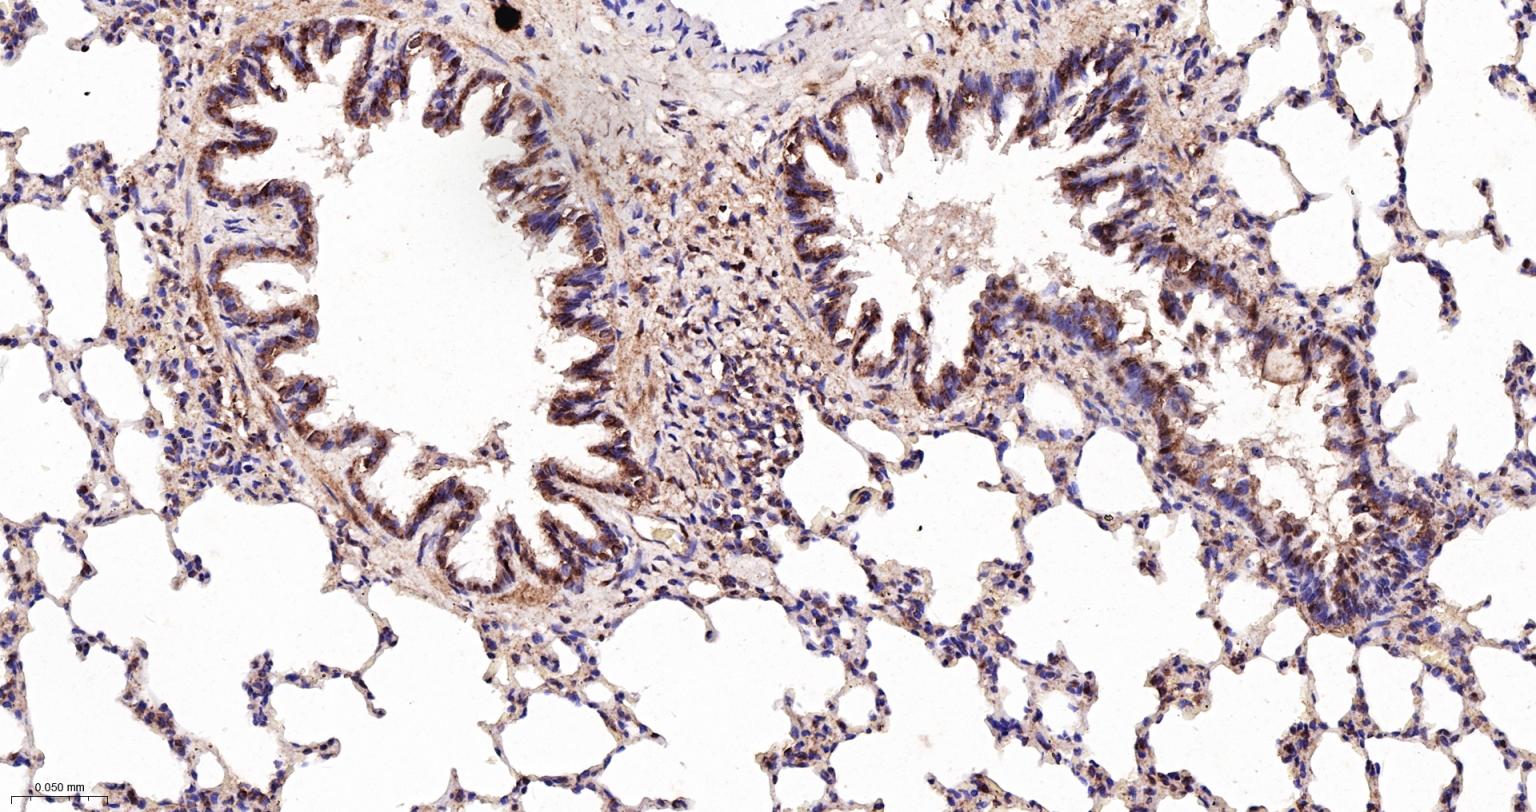

Paraformaldehyde-fixed, paraffin embedded Rat Lung; Antigen retrieval by boiling in sodium citrate buffer (pH6.0) for 15 min; The section was incubated with MAD2L2 Monoclonal Antibody, Unconjugated (bsm-61670R) at 1:200 overnight at 4°C, followed by conjugation to the bs-0295G-HRP and DAB (C-0010) staining.